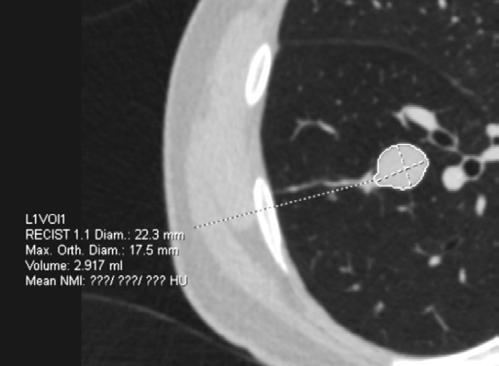

La TC de baja dosis, es la modalidad de imagen más utilizada como método de escrutinio para la detección de lesiones pulmonares, es un estudio rápido, que no requiere preparación previa. ESCANERS DE UN PACIENTE CON

Figura 1-4. Estudio de tomografía simple de tórax, con reconstrucción volumétrica, multiplanares con ventana para pulmón y en mediastino (, en donde se observa el nódulo pulmonar sólido de bordes lobulados hipodensos.

Se presente al caso de un masculino de 80 años de edad que acude por presentar tos en estudio de 3 meses de evolución, sin datos de fatiga, como antecedente de importancia tabaquismo por lapso de 40 años a razón de 1 cajetilla y media diaria (exposición de 60 paquetes año), actualmente suspendido.

Se le realiza estudio de tomografía simple de tórax en donde se encontró en el segmento anterior del lóbulo inferior derecho nódulo sólido, con diámetro de 22mm, volumen de 2.9ml, condiciona disminución del bronquio segmentario, con secreciones endoluminales distales, de acuerdo a la clasificación de LUNG RADS con categoría 4B, alta sospecha de malignidad. Sin evidencia de lesiones nodulares en el resto del parénquima.

Posteriormente, se realiza estudio de PET-CT con 18FDG , con hallazgos de metabolismo asociado y SULmax de 2.0, se recomienda realizar biopsia.

Se realiza cirugía con lobectomía inferior derecha, con resultado histopatológico de tumor carcinoide atípico, se realiza seguimiento con tomografía simple de tórax sin complicaciones en el lecho quirúrgico.

Figura 5. Estudio de PET-CT con FDG que muestra hipercaptación del radiofármaco en el nódulo pulmonar, lo que traduce en metabolismo aumentado.

Figura 6. Estudio de seguimiento postlobotomía.